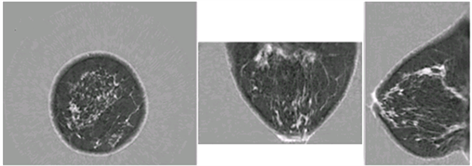

<em>Images showing coronal, axial, and sagittal speed of sound images of the breast, taken with the QT Imaging scanner.</em>

Images showing coronal, axial, and sagittal speed of sound images of the breast, taken with the QT Imaging scanner.